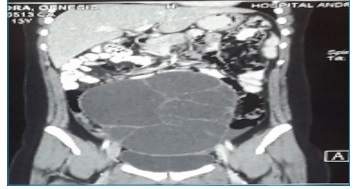

Adolescente de 13 años sin menarquia con dolor abdominal de 4 meses evolución, constipación y aumento del diámetro abdominal, un mes antes del ingreso nota la presencia de una masa dura en región de hipogastrio que se extiende desde la pelvis hasta la región umbilical. La ecografía abdominal evidenció una masa que ocupa todo hipogastrio (figura N°1), la tomografía abdominal mostró una masa dependiente de ovario 15cm de diámetro (figura N°2). Se realizaron los siguientes marcadores tumorales, CA 125, CA 199, ALFAFETROPROTENINA, BHCG, LDH cuyos resultados fueron normales.

Con esos resultados se sospechó de patología benigna de ovario por lo que se realizó laparotomía exploratoria con resección de masa de 15X10X5cm (figura N°3) dependiente de ovario derecho cuyo resultado de anatomía patológica fue cistoadenoma mucinoso de ovario con células endocervicales (figura N°4).

Masa multilobulada de apariencia quística dependiente de anexo derecho de 20 x 15 x 18 cm.